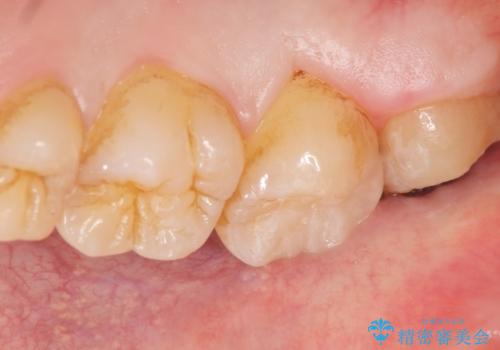

自然な仕上がりと使用感にご満足頂けました。

患者様のQOLが上がり、他の歯の治療やホワイトニングもご希望されました。

セルフメンテナンスの重要性もご理解頂き、今後親知らずの抜歯も行う予定です。

詰め物の種類:セラミックインレー (e-max press)